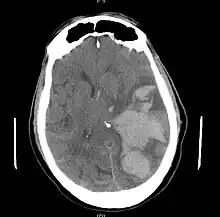

| MRI showing injury due to brain herniation | |

Treatment involves removal of the etiologic mass and decompressive craniectomy. Brain herniation can cause severe disability or death. In fact, when herniation is visible on a CT scan, the prognosis for a meaningful recovery of neurological function is poor.[2] The patient may become paralyzed on the same side as the lesion causing the pressure, or damage to parts of the brain caused by herniation may cause paralysis on the side opposite the lesion.[11] Damage to the midbrain, which contains the reticular activating network which regulates consciousness, will result in coma.[11] Damage to the cardio-respiratory centers in the medulla oblongata will cause respiratory arrest and (secondarily) cardiac arrest.[11] Investigation is underway regarding the use of neuroprotective agents during the prolonged post-traumatic period of brain hypersensitivity associated with the syndrome.[17]